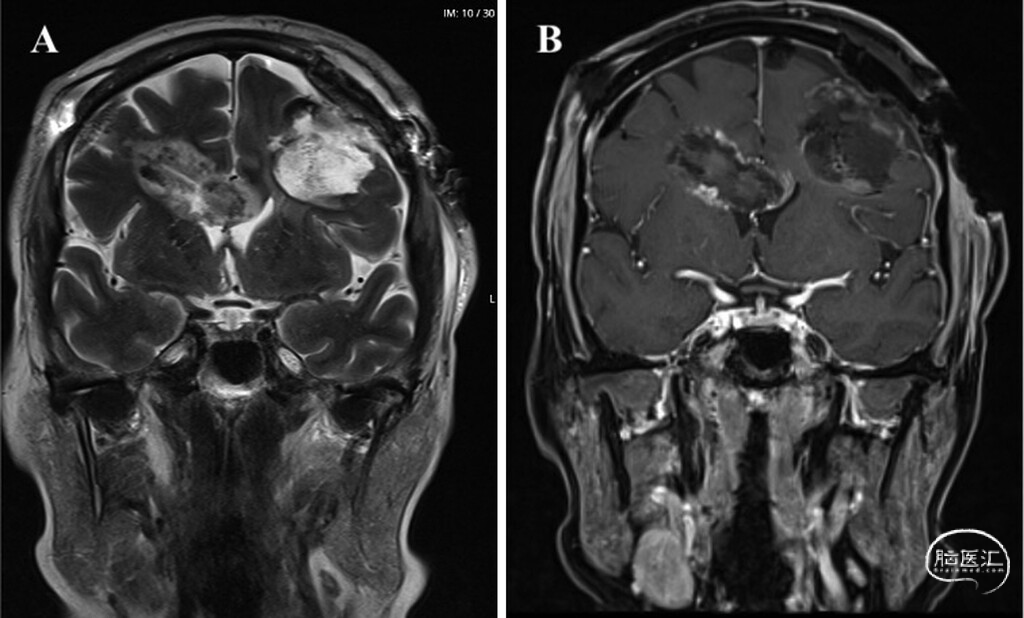

● 病例1:2024年8月随访影像提示脑室旁区域出现放射性坏死,遂启动贝伐珠单抗治疗,患者临床症状随后改善。术后20个月随访MRI未见肿瘤复发(图5),患者目前临床状态稳定。

图5:病例1术后20个月随访MRI。A:冠状位T2加权像显示右侧脑室旁LITT消融残腔及左侧额叶切除术后残腔。B:冠状位增强T1加权像显示两处治疗残腔均无肿瘤进展迹象。